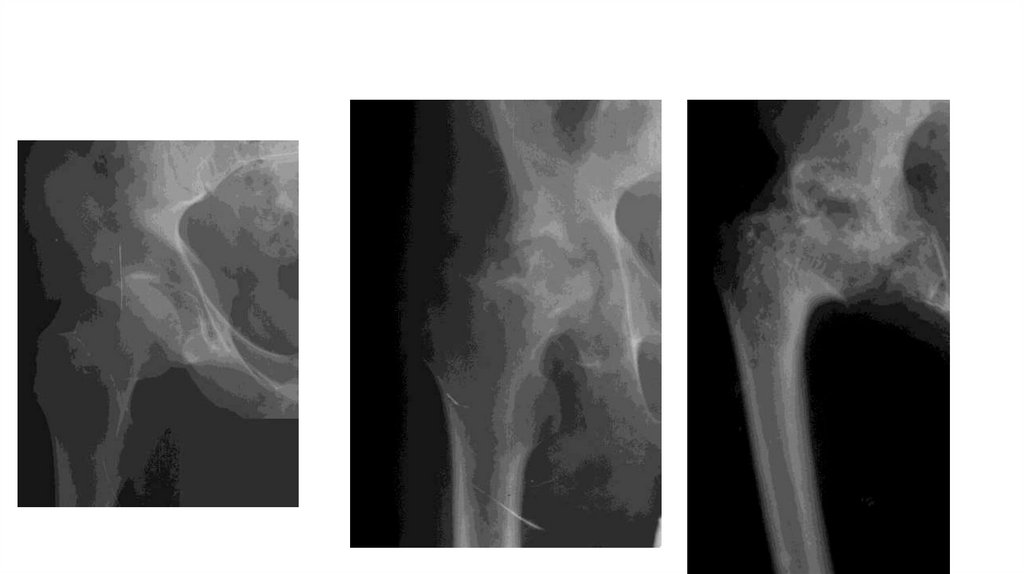

«Воспалительные

заболевания опорнодвигательного аппарата»